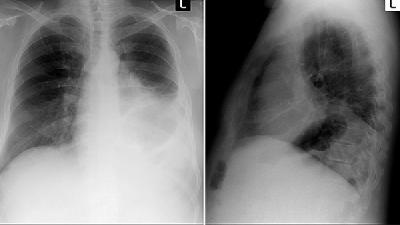

26岁的梁生最近正忙于研究生毕业实验,结果不小心感冒了,又发烧又咳嗽,还越来越严重,到医院一检查才知道自己患上了病毒性肺炎梁生就诊时,症状如下:发热、咳嗽、气促、咳时胸痛,痰少口干,口唇轻度发绀两天未解大便,尿黄,舌红苔黄腻,脉洪大。相关检查显示:体温39.3C,,心率105次/min,律整,双肺闻及少许湿啰音、呼吸32次/min,血压15/9kPa;血常规...